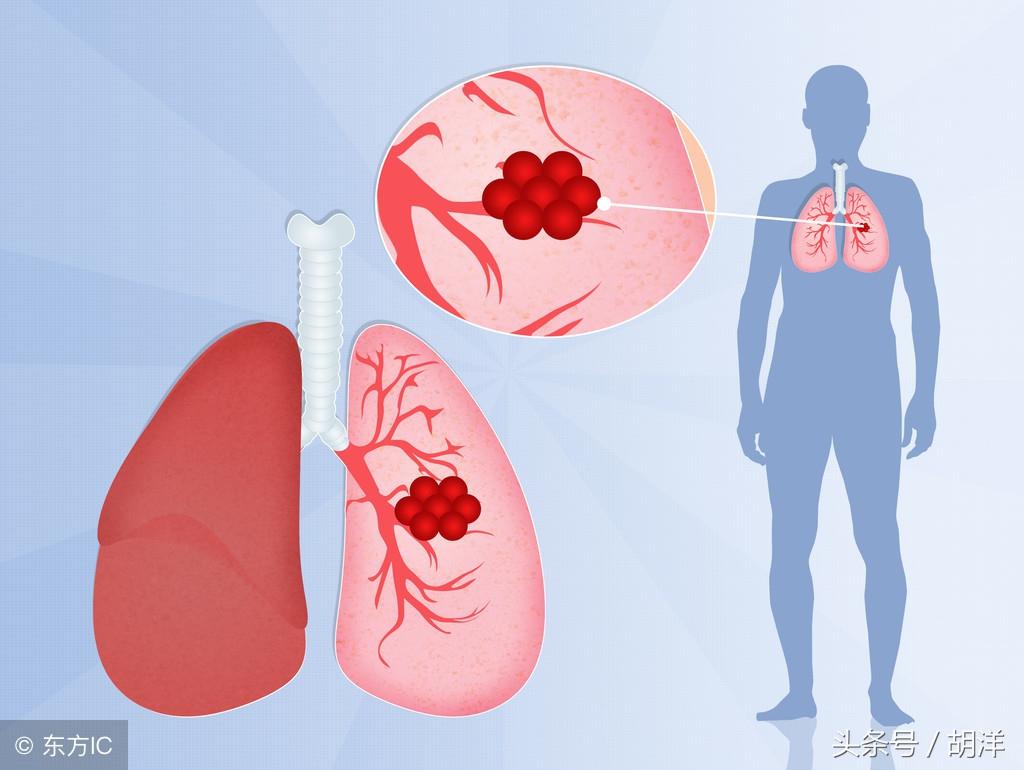

肺癌

肺癌也是较为常见的导致咯血的原因,恶性肿瘤细胞对于肺组织的侵蚀是其他疾病无法比拟的,几乎可以侵犯肺部正常组织中的所有结构,包括血管,另外,肺癌癌肿由于生长过快,其表面的细胞可能会因为得不到充足的血液供应而坏死,这样的坏死很容易产生渗血,是引起痰中带血的常见原因。